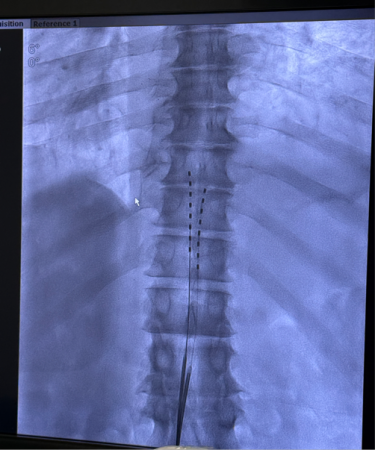

电极植入到位

手术在DSA(数字减影血管造影)引导下开展,在肖红主任医师指导下,由银燕护师、卢帆助理研究员组成的手术团队精准将电极送达患者相应节段的硬膜外腔,并在术中完成刺激参数调试。T先生当场反馈,电刺激覆盖范围与疼痛区域高度重合,镇痛效果立竿见影,手术过程顺利完成。